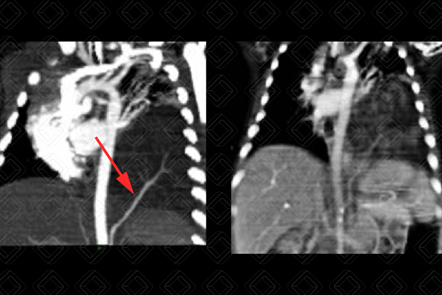

Texto alternativo para a imagem Créditos: Dra. Elazir Mota - Rio de Janeiro/RJ

Descrição da figura: Tomografia computadorizada do tórax após injeção do contraste venoso, evidenciando opacidade no lobo inferior esquerdo (LIE) e vaso anômalo (seta vermelha), que tem sua origem no abdome, mas atravessa e alcança a lesão no LIE, achado que caracteriza a lesão como sequestro pulmonar.

• Tomografia computadorizada do tórax: A tomografia computadorizada com o uso do contraste venoso confirma o diagnóstico, mostrando o suprimento arterial anômalo no segmento pulmonar acometido (figura);